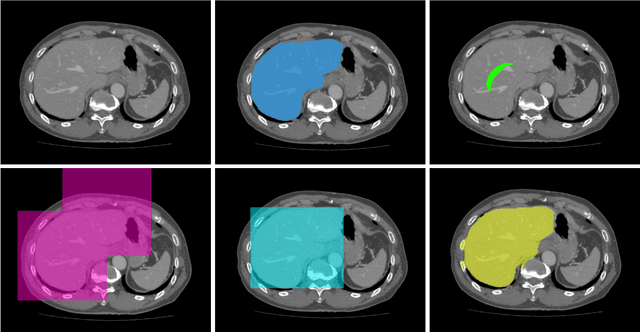

To efficiently establish training databases for machine learning methods, collaborative and crowdsourcing platforms have been investigated to collectively tackle the annotation effort. However, when this concept is ported to the medical imaging domain, reading expertise will have a direct impact on the annotation accuracy. In this study, we examine the impact of expertise and the amount of available annotations on the accuracy outcome of a liver segmentation problem in an abdominal computed tomography (CT) image database. In controlled experiments, we study this impact for different types of weak annotations. To address the decrease in accuracy associated with lower expertise, we propose a method for outlier correction making use of a weakly labelled atlas. Using this approach, we demonstrate that weak annotations subject to high error rates can achieve a similarly high accuracy as state-of-the-art multi-atlas segmentation approaches relying on a large amount of expert manual segmentations. Annotations of this nature can realistically be obtained from a non-expert crowd and can potentially enable crowdsourcing of weak annotation tasks for medical image analysis.